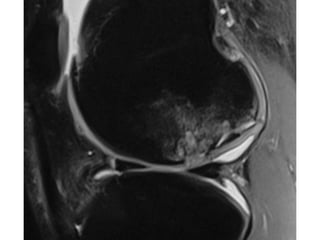

The document presents a detailed case study of a patient with transient osteoporosis of the hip (TOH) and spontaneous osteonecrosis of the knee (SONK) treated at Choithram Hospital & Research Centre in India. Over 20 years, the patient experienced multiple episodes of TOH and SONK with no history of trauma or co-morbidities, resulting in resolutions and recurrences of conditions. The information is intended for orthopedic surgery students and highlights personal experiences and case collections, with a disclaimer regarding content usage and potential controversies.